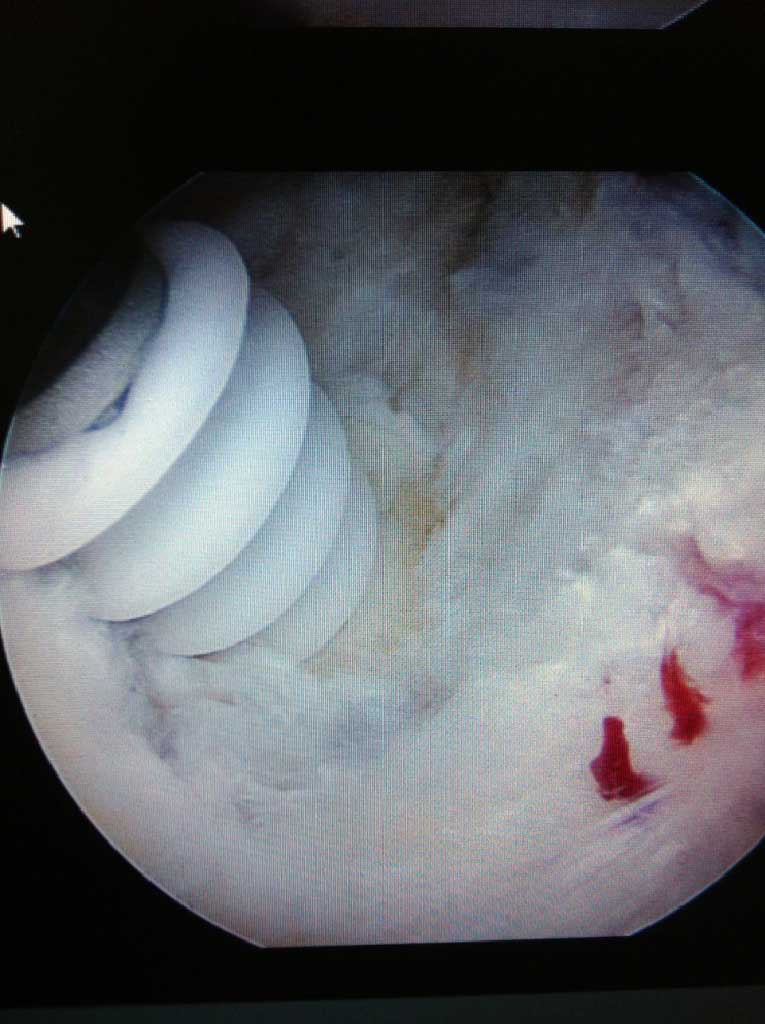

Je nach Alter, Verletzungsmuster, Anzahl der Luxationsereingnisse und weiteren Faktoren, wird eine schulterstabilisierende Operation indiziert und empfohlen. Diese führen wir ebenfalls ausschliesslich arthroskopisch

(Schüsselloch Operation) durch. Innerhalb von 15 - 30 min wird dabei der knorpelige Ring (s.g. Labrum) auf den knöchernen Pfannenrand mit speziellen Anker und Fäden wieder zurück befestigt.

Die Nachbehandlung richtet sich nach Schwergrad der operativ versorgten Verletzungen, beträgt allerdings in d.R. nicht länger als 8-10 Wochen, inkl. Rückkehr zu Kontaktsportarten binnen 12 Wochen nach Operation.